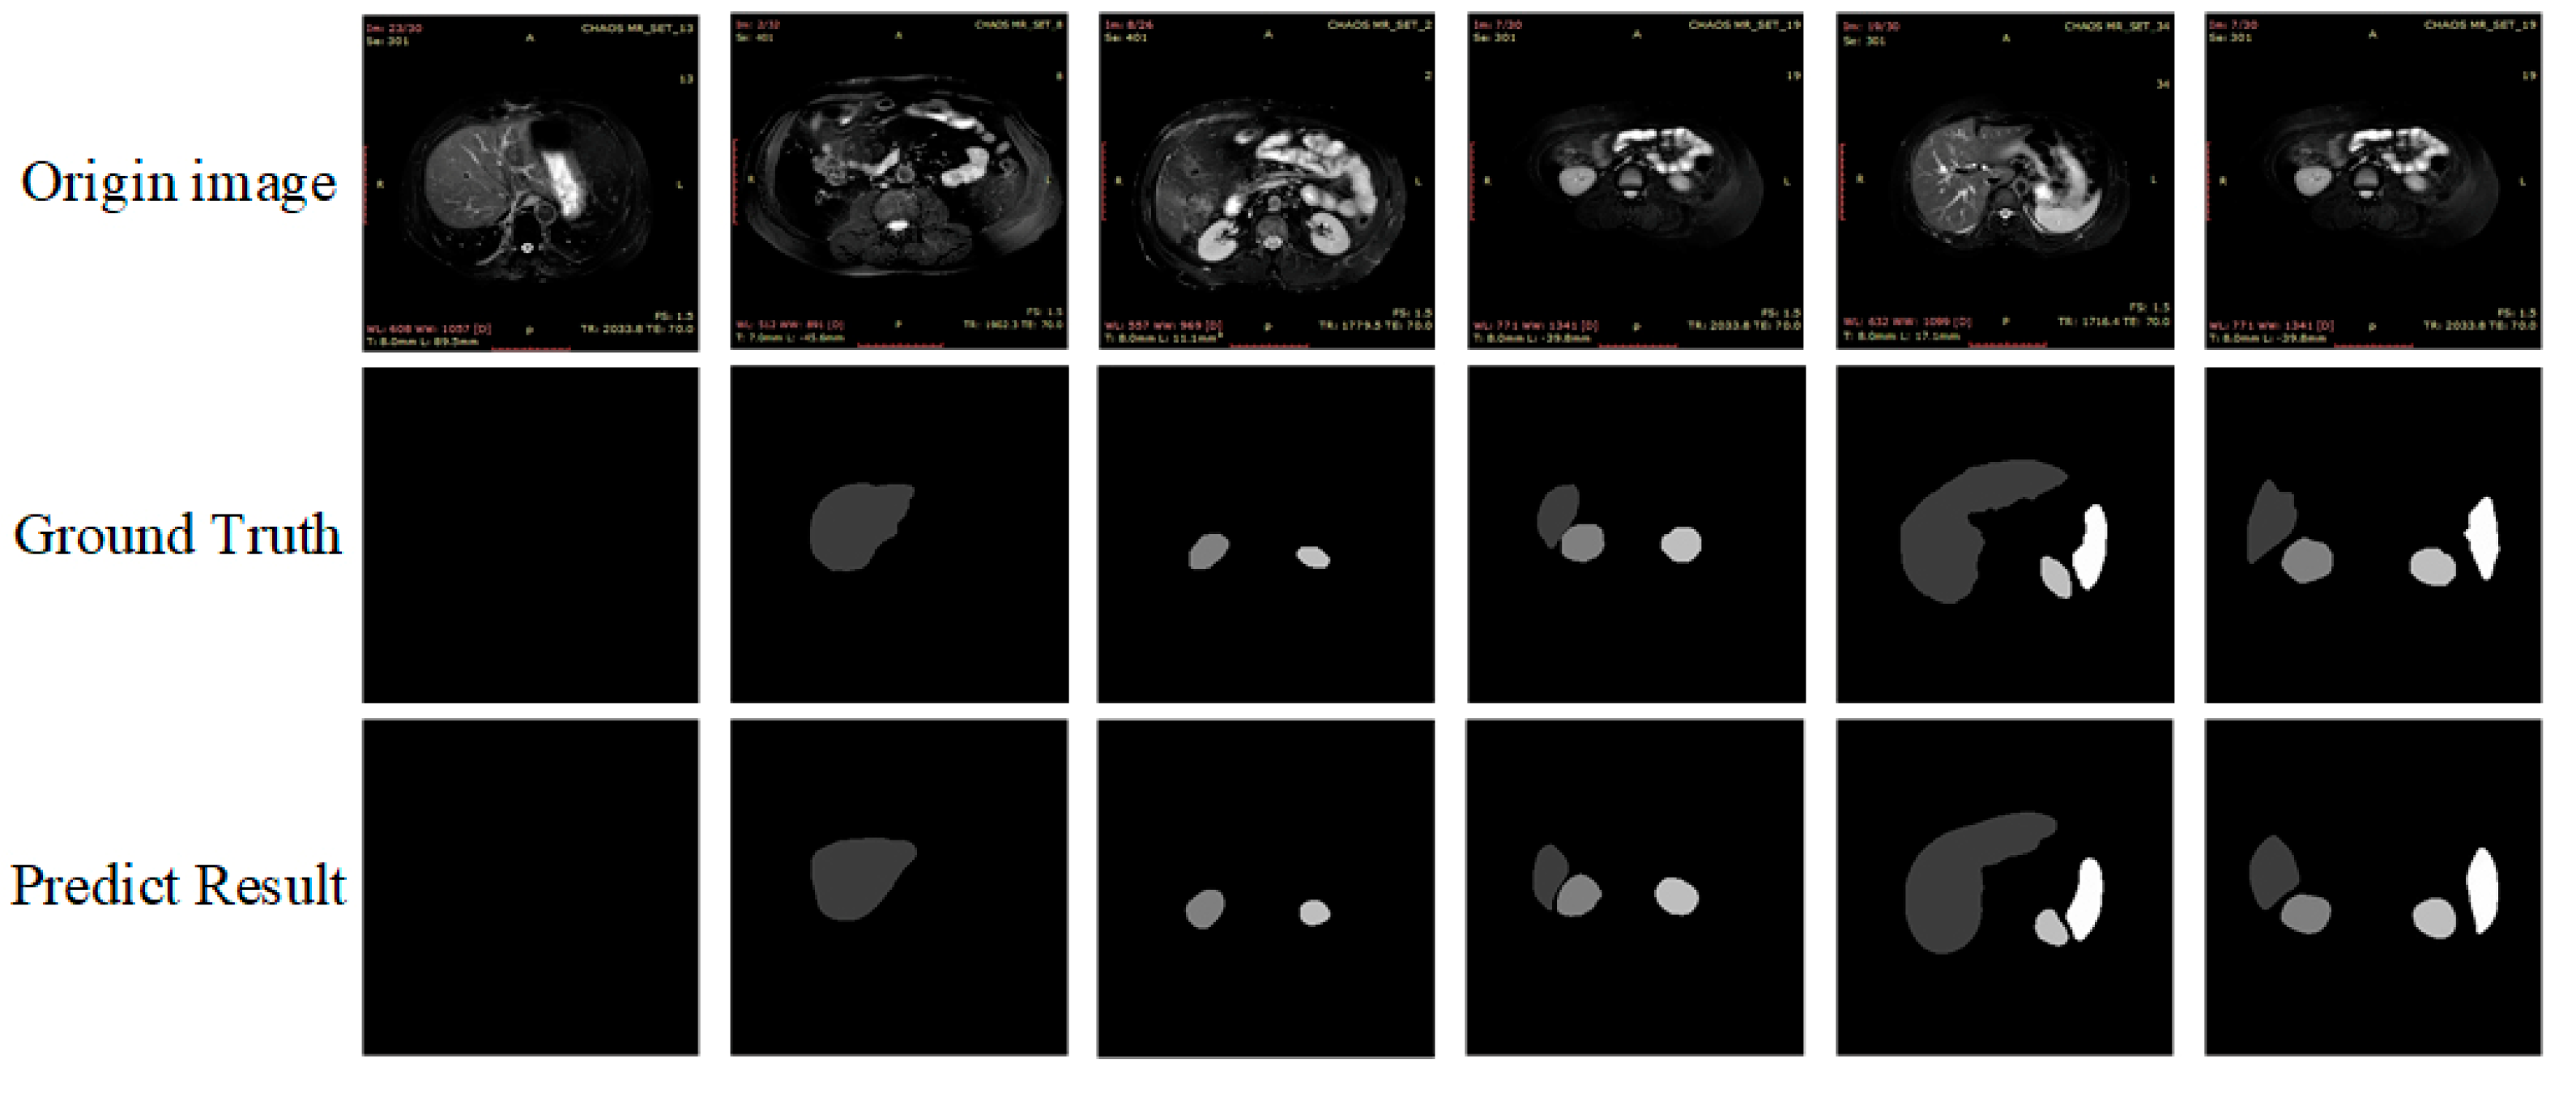

As can be seen in Table 6, the mIoU and mPA values of the ResNet50 backbone PSPNet network are 81.04% and 89.66%, respectively, lower than the algorithm in this paper by 1.28% and 0.44%, respectively. While the mIoU values of PSPNet and Deeplabv3+ networks using MobileNetV2 [53] backbones are 76.41% and 75.92%, which were lower than the algorithm in this paper by 5.92% and 6.41%, respectively. The mPA values were 87.02% and 86.04%, lower than the algorithm in this paper by 3.08% and 4.06%, respectively. We also found some dedicated algorithms for MRI 2d images for comparison. mIoU and mPA values for M-FCN are 77.21 and 86.40, respectively—5.12% and 3.7% lower than the algorithm in this paper. mIoU and mPA values for U-Net_based are 77.86 and 85.14, respectively, 4.47% and 4.96%, lower than the algorithm in this paper, respectively. The prediction plots of organ segmentation for each algorithm are shown in Figure 11.

Figure 11.

The prediction plots of organ segmentation for each algorithm.

As shown in Figure 11 above, based on visual observation, the algorithm in this paper is closest to the gold standard in terms of organ edge structure, and there are no organ prediction errors and more well-defined angles.

However, at the same time, we observed segmentation errors in the above VGG prediction result maps and PSPNet, and MobileNetV2 backbone prediction images, which all showed incorrect predictions of liver images in the third set of image predictions, of which we analyzed the reasons as follows:

We use CI-UNet to make predictions for each of the above six typical images, and the prediction results are shown in Figure 13.

Figure 13.

Segmentation prediction results of CI-UNet for typical images.